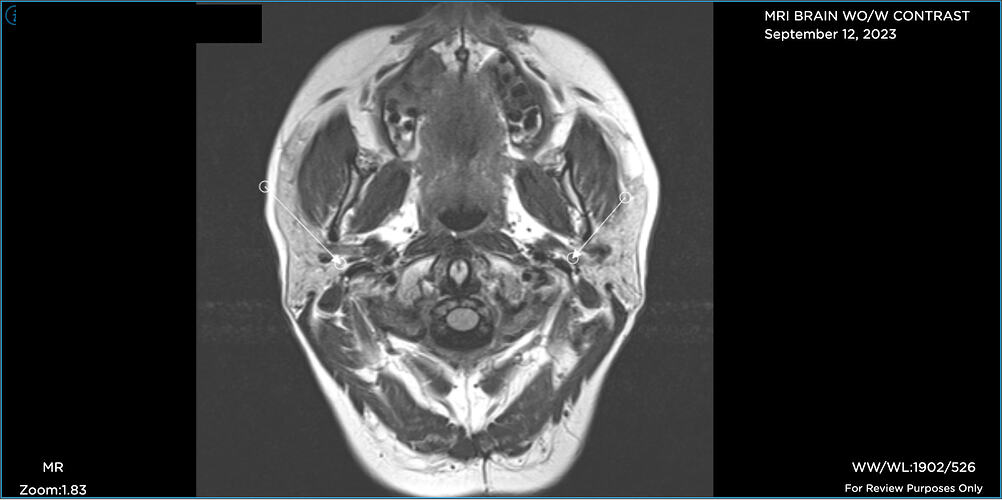

Hi folks. Like many of you, I’ve been on a miserable journey for years now. I’m just diagnosed “officially” with Eagles yet, but my provider said she sees elongated styloids on both sides, and she has referred me to Hepworth and recommends styloidecomy(ies).

Prior to seeing her, I’d been dealing with a CSF leak (5 blood patches to date), chronic migraines, Central Sensitization Syndrome/fibro (basically whole body pain), etc. When my FMC looked at the imaging I finally uploaded, she immediately noticed elongated styloids on both sides and she recommends styloidectomy(ies).